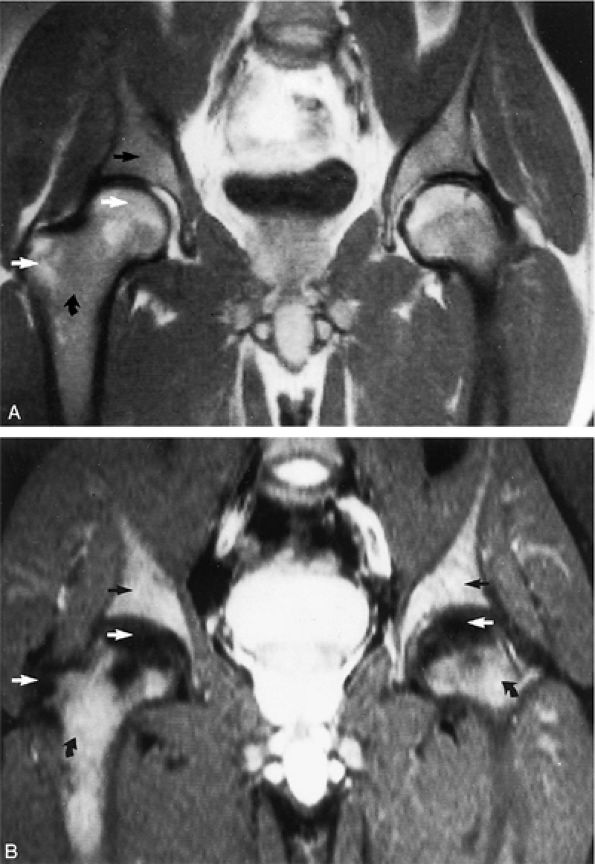

FIGURE 13.18 ● In chronic myelogenous leu-kemia, diffuse marrow involvement infiltrates regions of previous red marrow stores in the femurs (curved arrows) and acetabulum (straight black arrows) and demonstrates low signal intensity on a T1-weighted image (A) and high signal intensity on a corresponding STIR image (B). The sites where yellow marrow is spared (the greater trochanter and femoral epiphysis) demonstrate high signal intensity on the T1-weighted image and low signal intensity (from the nulled fat signal) on the STIR sequence (white arrows).